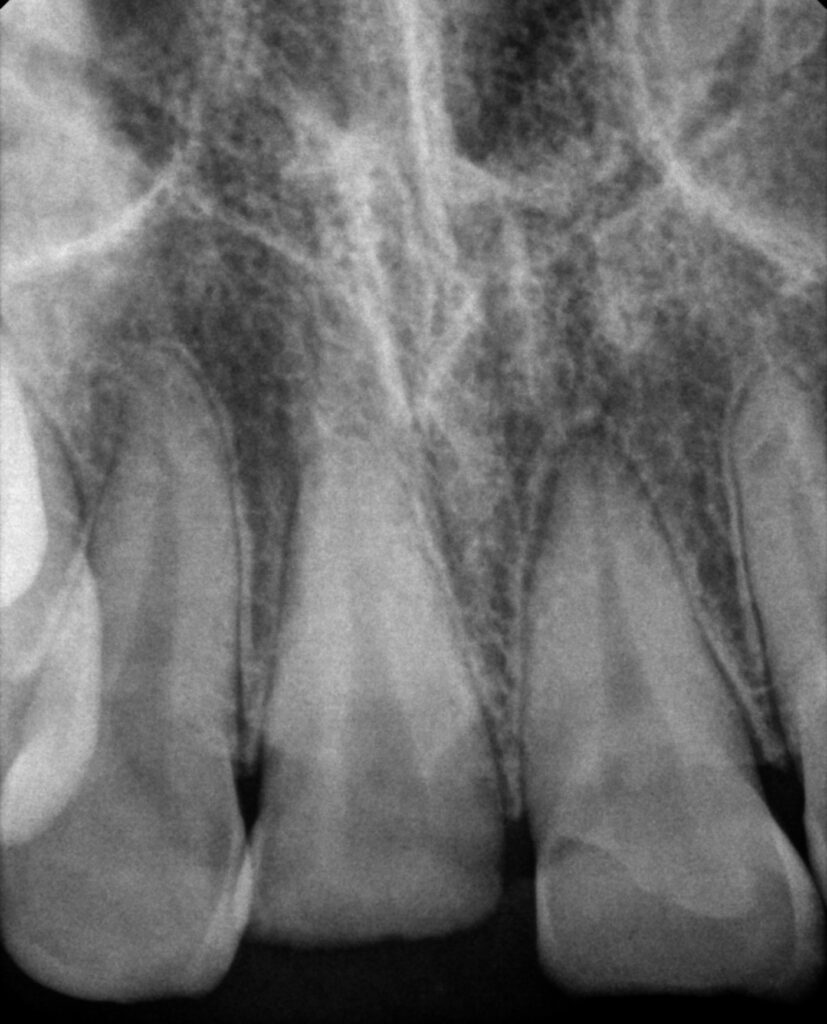

치아 외상으로 인해

크게 이가 부러졌다면,

방사선 촬영을 통해

이를 잡아주는 치조골에는

문제가 없는지 확인을 해야 되는데요.

2025.02.12

촬영본을 확인해 보았을 때

협측 치조골의 골절이 있는 것으로 보아

이가 흔들릴 것으로 판단되며,

치아 고정술이 필요해 보입니다.